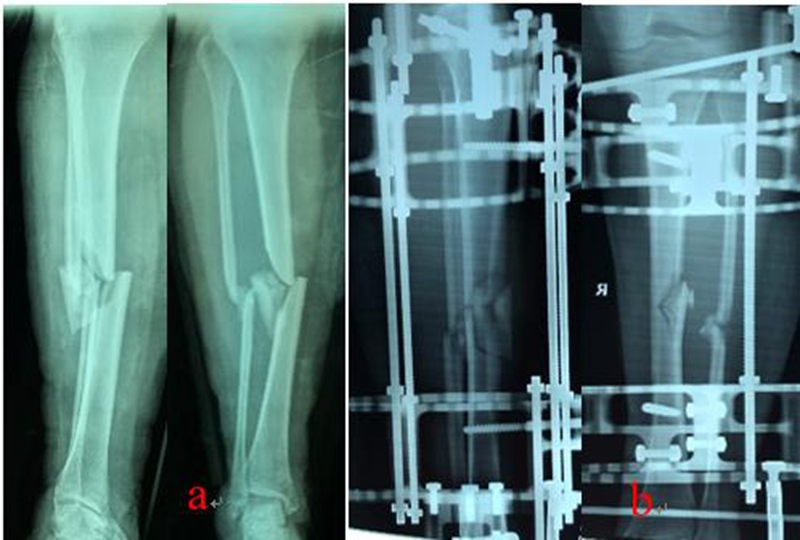

乔锋等[7-9]利用自主研发的3D打印骨科外固定架(QF)和数字六轴外架(QSF)治疗胫骨骨折,获得良好的临床疗效。3D打印骨科外固定架具有自动复位骨折功能,4根螺纹连接杆与骨的轴线平行,通过旋拧调节螺母,调节两个固定环之间的距离,实现对骨折断端轴向应力的调节和固定方式的转换,早期坚强固定,中期加压固定,后期弹性固定。复位过程无需透视,不依赖医生经验,手术时间短,可以不用麻醉,术后即可完全负重下地行走,复位精确,固定合理,操作简便。数字六轴外架QSF配套软件基于CT数据,与国际同类产品比较,复位精确,固定牢靠,操作简便,学习曲线短。

图1:QF治疗胫腓骨骨折

图2:QSF治疗胫腓骨骨折